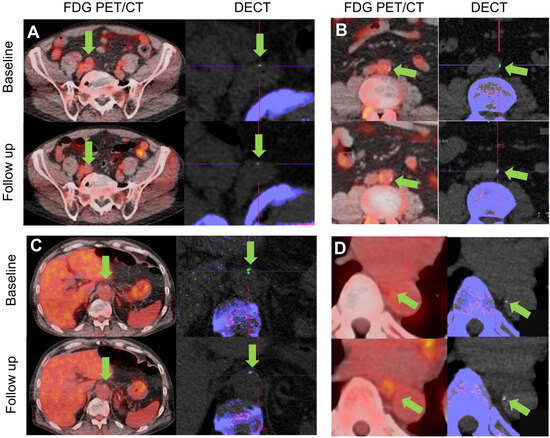

Representative 18F-FDG PET/CT and DECT images before and after Pegloticase treatment are shown in Figure 4. One patient demonstrated complete resolution of an MSU-coded deposit located in their abdominal aorta following Pegloticase treatment.

Figure 4.

Representative PET/CT (left) and DECT images (right) from axial locations in five vessel levels in four patients. (A) 18F-FDG uptake (orange overlay) shows inflammation in the right iliac artery (green arrow). On DECT, MSU-coded deposits (green) are shown in the corresponding vessel walls (green arrow), with bone (calcium) shown in purple. In this location, imaging shows a decrease in 18F-FDG uptake and MSU volume from baseline to follow-up following treatment with Pegloticase. (B) 18F-FDG uptake showing inflammation and DECT showing an MSU-coded deposit in the abdominal aorta (green arrows). In this patient, the deposit which was identified as MSU-coded at baseline, which likely had mixed calcium and MSU characteristics, appeared to resolve after treatment. 18F-FDG uptake in a small segment (~2 cm) of vessel centered on the location of the MSU-coded deposit showed a reduction in SUVmean from 1.81 to 1.68 and in SUVmax from 2.60 to 2.55. (C) 18F-FDG uptake in the abdominal aorta (green arrow) is reduced at follow-up (SUVmean/SUVmax pre: 1.65/2.17, post: 1.57/2.00) while MSU-coded deposit resolves. (D) In the descending thoracic aorta, little change is seen in 18F-FDG signal (SUVmean/SUVmax pre: 1.69/2.24, post: 1.64/2.26) while MSU-coded deposit volume increases from 1.3 mm3 to 3.4 mm3. (E) In the left femoral artery another MSU deposit resolves after treatment while 18F-FDG signal reduces slightly (SUVmean/SUVmax pre: 1.64/2.30, post: 1.64/2.25).